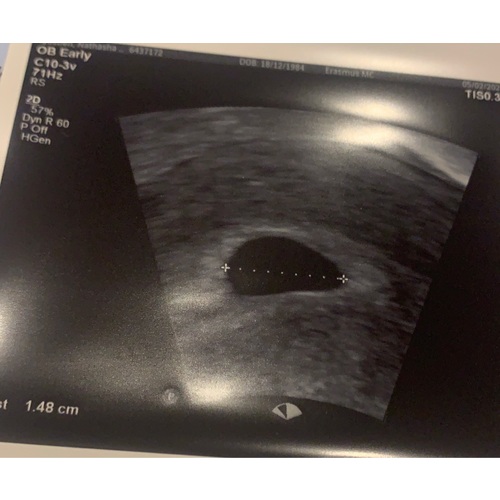

Ja, ze gaf aan was een jonge dame. Ik zeg niet dat ze haar werk niet goed doet maar ik zag wel iets. Maar ze bleef zeggen “ ik zou nu al een kloppend hartje moeten zien.” Maar vruchtzakje is wel gegroeid. Ik wil zelf doorgaan met de utrogestan maar ik weet het allemaal niet meer. Ben zo in de war...

Erasmus Rotterdam

Ik heb twee weken geleden ook echo gehad waar niks op te zien was 6 dagen later was er wel een vruchtje te zien met een kloppend hartje 🤞 ik ga voor je duimen dat het als nog goed komt ❤

Ik was 6.2 dagen en had dezelfde echo.. Ik moest wel doorgaan.. Ik werd teruggeplaatst naar 5.4 en moest de week erna terug komen.. En toen had ik er wel iets in.. Ik had 31-12 een terug plaatsing